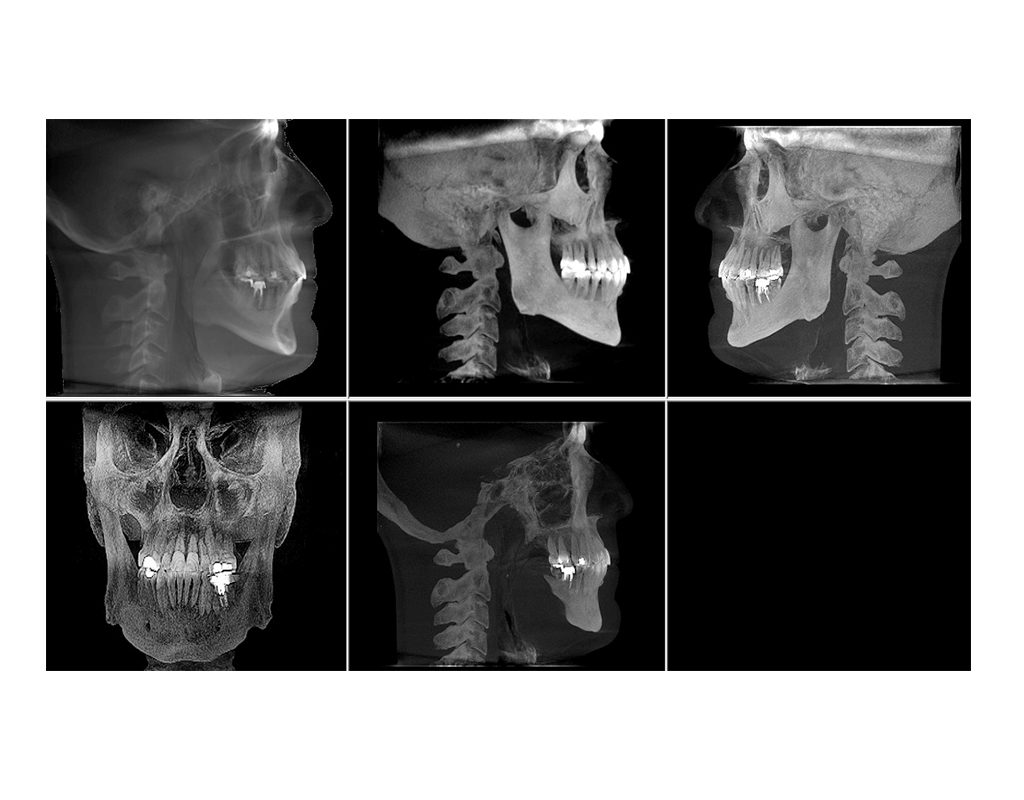

Tomografía de Haz Cónico (CBCT)

Es una técnica radiográfica que genera imágenes tridimensionales (3D), con mucho detalle de los dientes, tejidos blandos y huesos de la región maxilofacial, resultando en una menor radiación y una alta resolución.